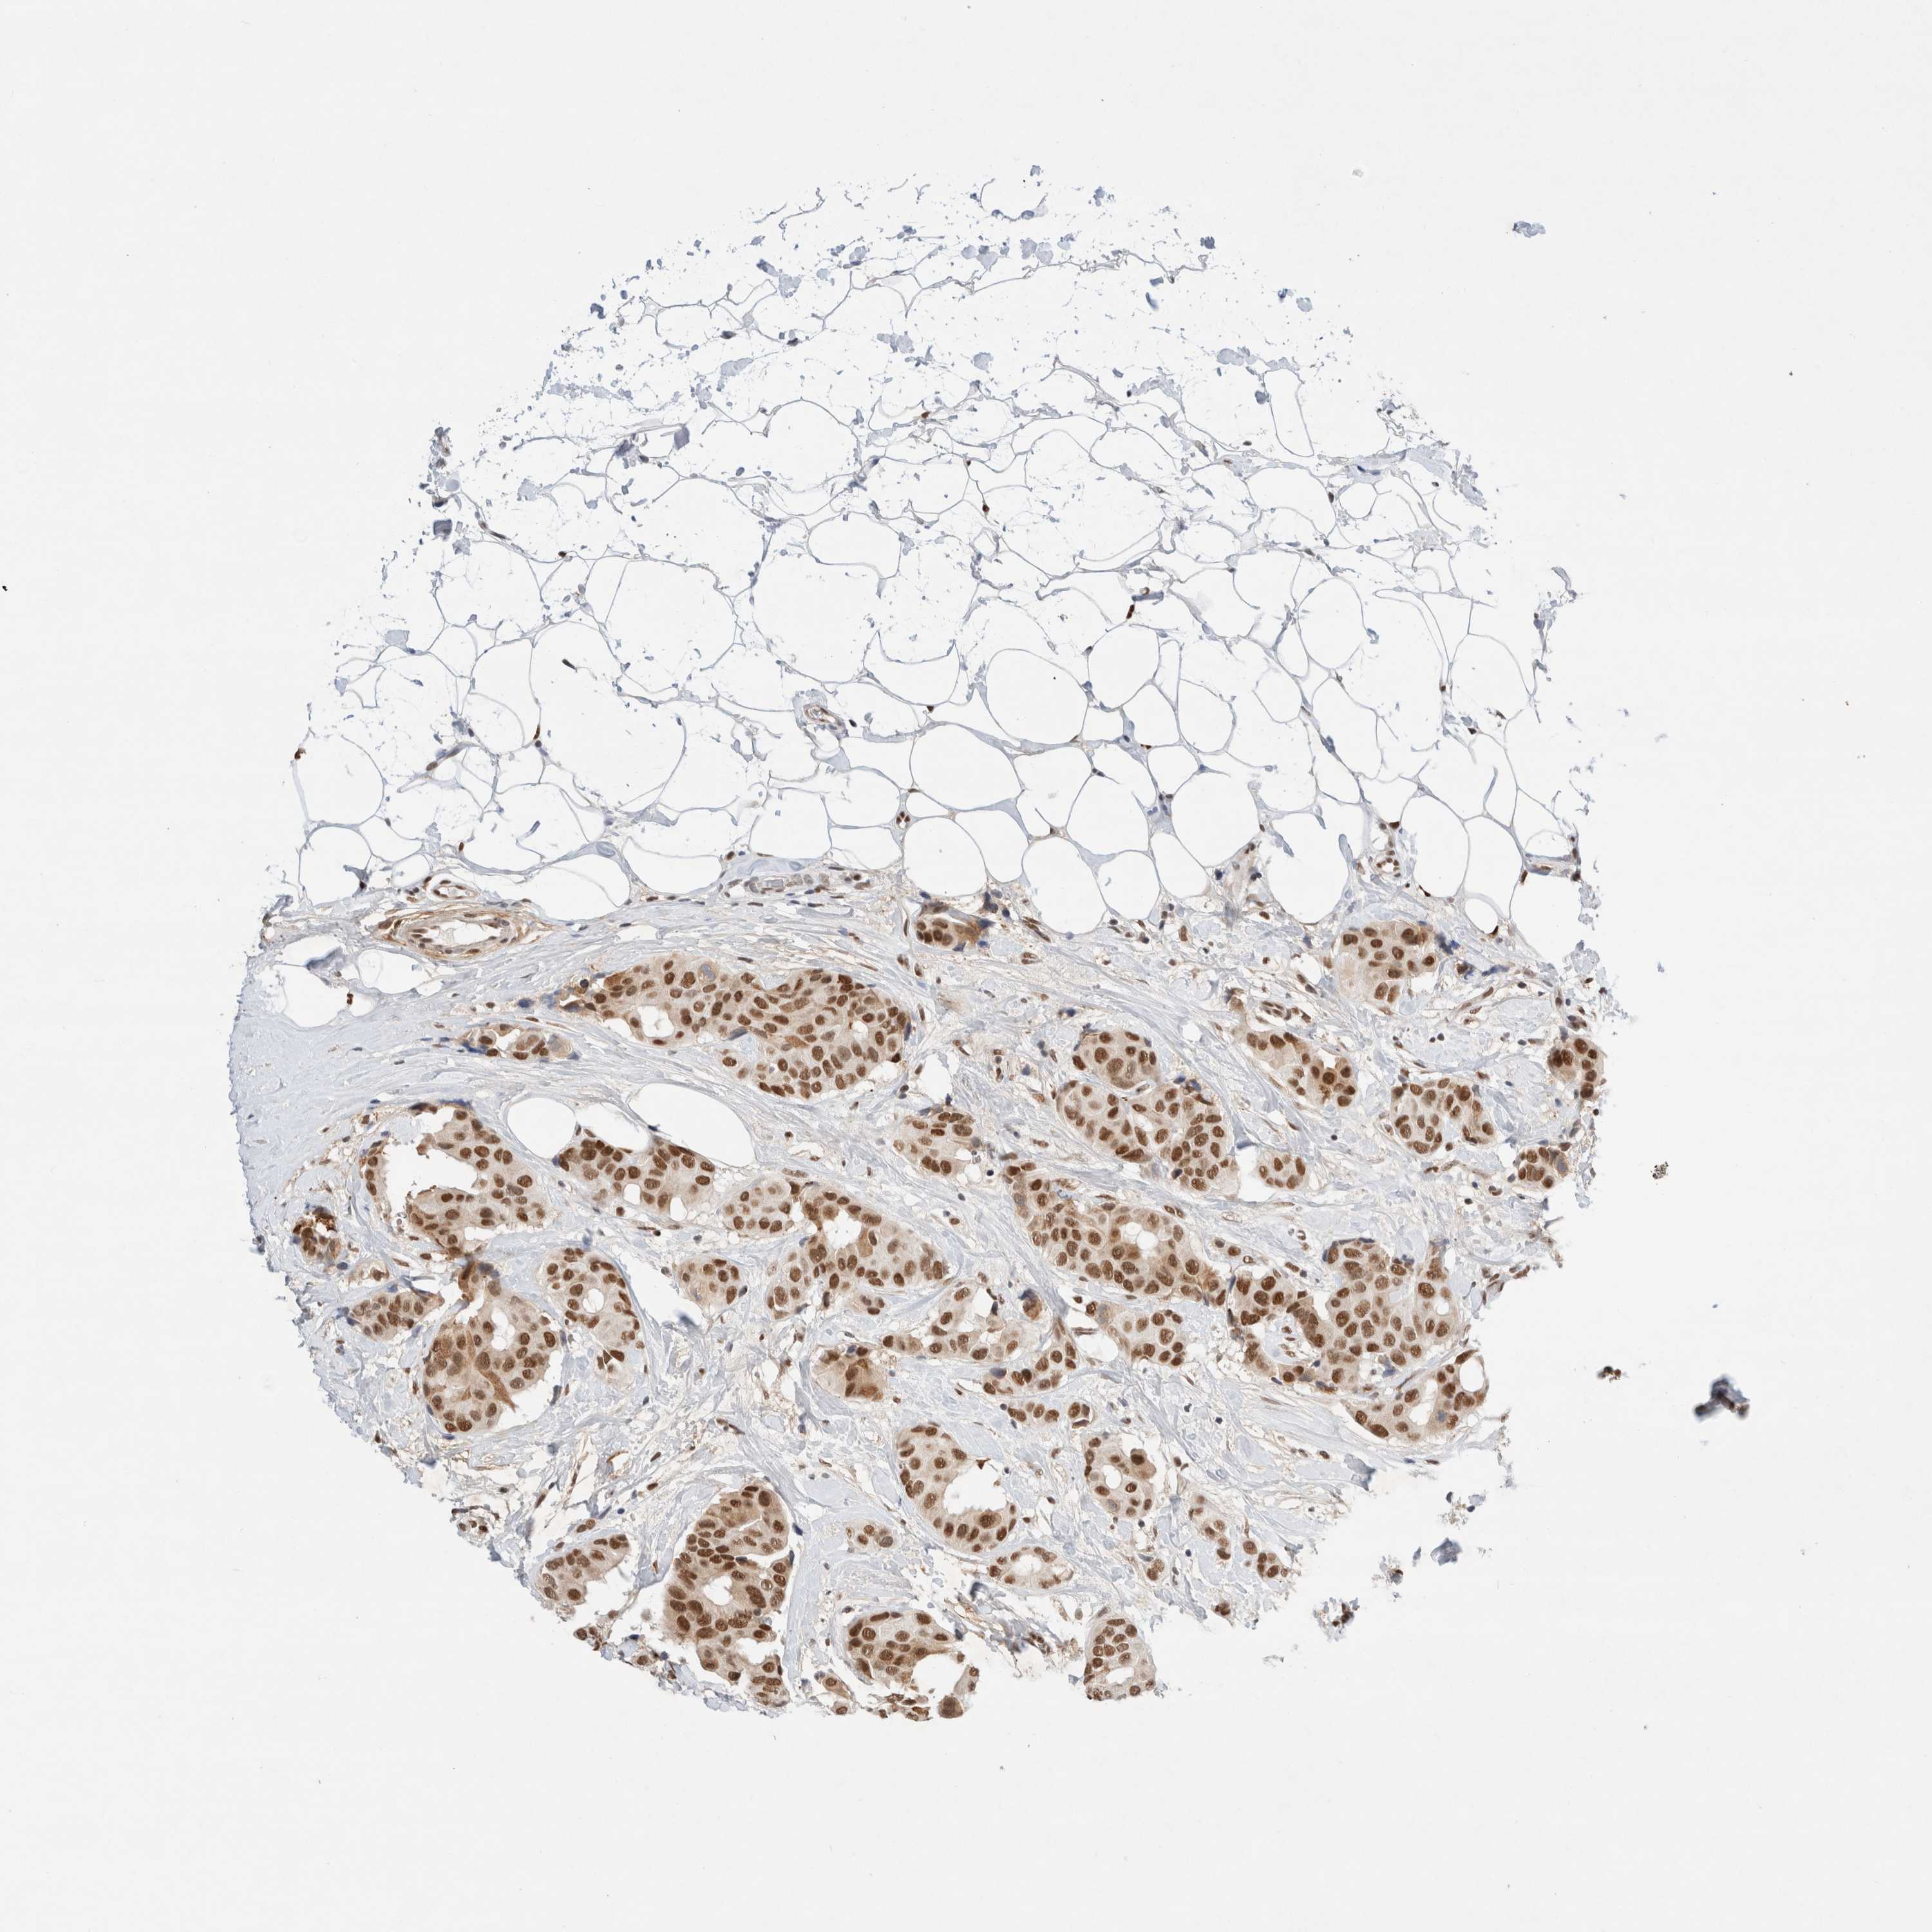

BRCA TCGA BRCA VALIDATION PROTEIN EXPRESSION

Breast cancer

Human cancer